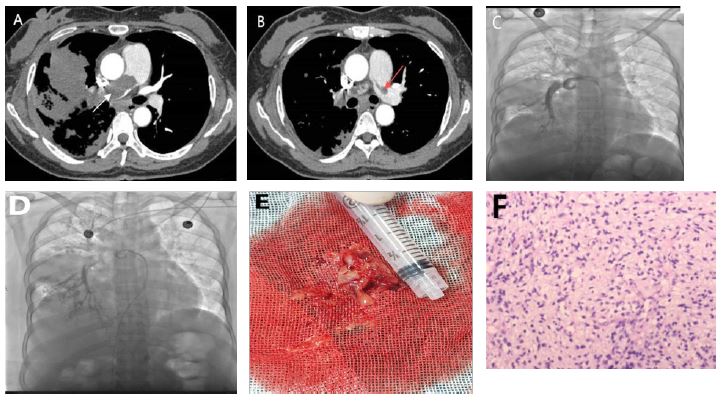

The patient gradually recovered after surgery and received three cycles of chemotherapy approximately one, two, and three months later. The specific dosages and schedules included: liposomal doxorubicin 60 mg on Day 1, dacarbazine 400 mg from Days 1 to 5, cyclophosphamide 100 mg on Day 1, and vincristine 1.6 mg on Day 1. After the third cycle of chemotherapy, the patient experienced a decrease in red blood cells and platelets. This indicated bone marrow suppression. Through active treatment and adequate rest, the patient gradually regained strength. Six months after surgery, the fourth cycle of chemotherapy was administered with an adjusted regimen of albumin-bound paclitaxel 150 mg on Days 1, 8, and 15. Additionally, radiotherapy was given to a gradually enlarging nodule in the left lung (Figure 3). The medical team subsequently administered targeted treatment using an anlotinib hydrochloride capsule. The patient was in good general condition and experienced no significant adverse reactions. Currently, the patient is stable, has an ECOG performance status of 1, and continues to receive oral targeted drug treatment.

Figure 3: (A-D) show chest CT images at 1 month, 2 months, 3 months, and 6 months after surgery, respectively. It can be seen that the nodule in the upper lobe of the left lung gradually increases.

This case highlights the importance of forming a rapid response team, including experts from radiology, vascular intervention, thoracic surgery, and molecular pathology, for managing pulmonary artery masses with fast-spreading pulmonary dissemination. Figure 3 illustrates that the multidisciplinary treatment approach reduced the time from diagnosis to surgery to just 12 days. This represents a 58% acceleration compared to traditional methods. This effective multidisciplinary model offers a novel clinical pathway to enhance the prognosis of these rare tumors.